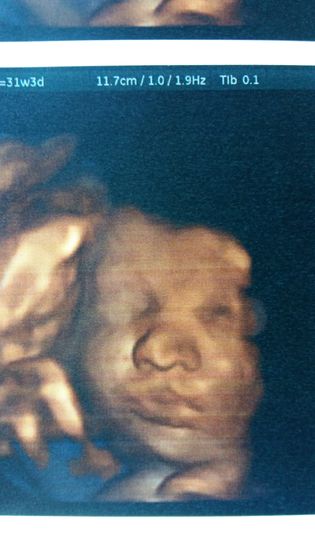

По узи 2-3 степень созревания плаценты. Кровоток и пуповина хорошие, справляются. Но для перестраховки положили в паталгию. Первый раз за 2 беременности меня положили. Обещают амнистировать в понедельник. 3 роддом это конечно ?… Вес дочки 1800. губки ПЮ уже делает)))) Прибавка в весе +15 кг.

Все будет хооошо!) губки прелесть на фото ??

Как прелесть! Я про фото ??! Держись, в целом не много осталось

Вашему УЗИсту надо еще и в фотографы податься))